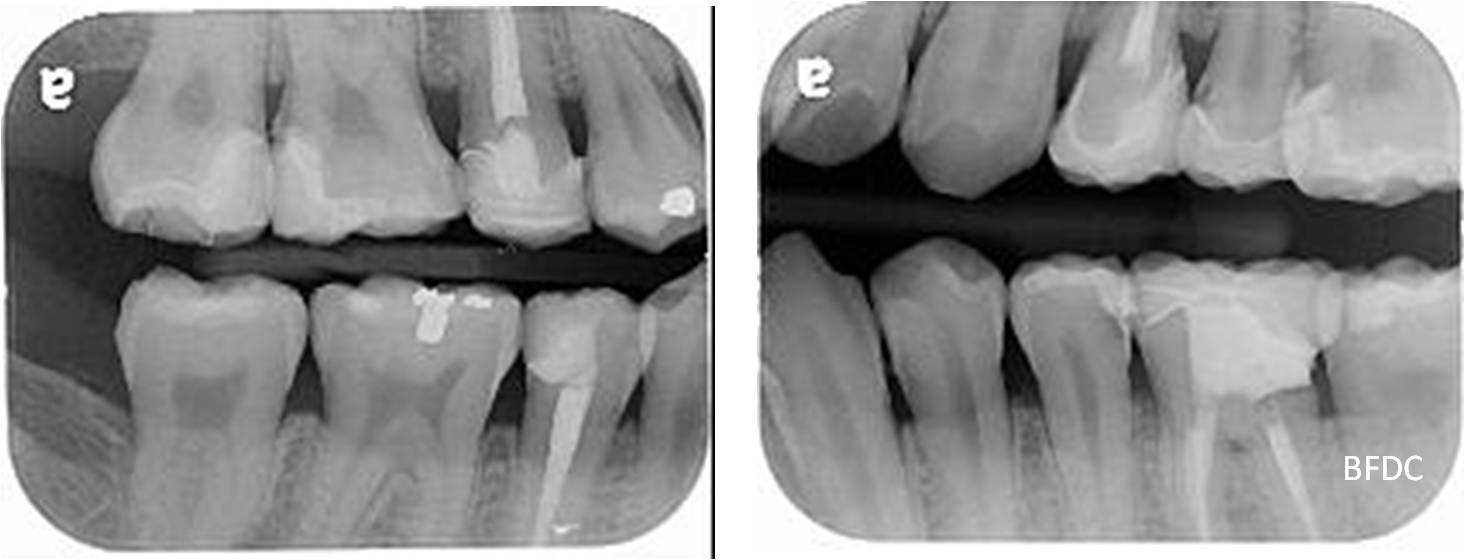

陶瓷崁體及冠蓋體-蛀牙-#1516172526 大範圍的補皮,該如何選擇,嵌體的方式就適用於大範圍的填補,因為它是一體成形, 嵌體材質多種,以往才會使用黃金合金,但因價格昂貴且顏色太過突出,因此現在多使用玻璃陶瓷二氧化鋯等材質的全瓷冠。嵌體有其優勢,因一體成形的材料,硬度和穩定性都較高,不用一點一點填補,減少下方凹陷重複蛀牙的危機,也不會變形或染色,美觀度高很多。 #1516172526蛀牙 #1516172526蛀牙 崁體及冠蓋體修形 安裝模型至咬合器 嵌體及冠塊體製作 陶瓷崁體及冠蓋體 黏著後 黏著後X光 術前、術後比較 嵌體有其優勢,因一體成形的材料,硬度和穩定性都較高,不用一點一點填補,減少下方凹陷重複蛀牙的危機,也不會變形或染色,美觀度高很多。

能避免片狀樹脂造成的,下方重複蛀牙,或彈性大造成咬合不舒服的問題,若有多顆牙齒填補,或坑陷較大者,如牙齒已蛀超過1/2或2/3者,才建議使用此種方式。